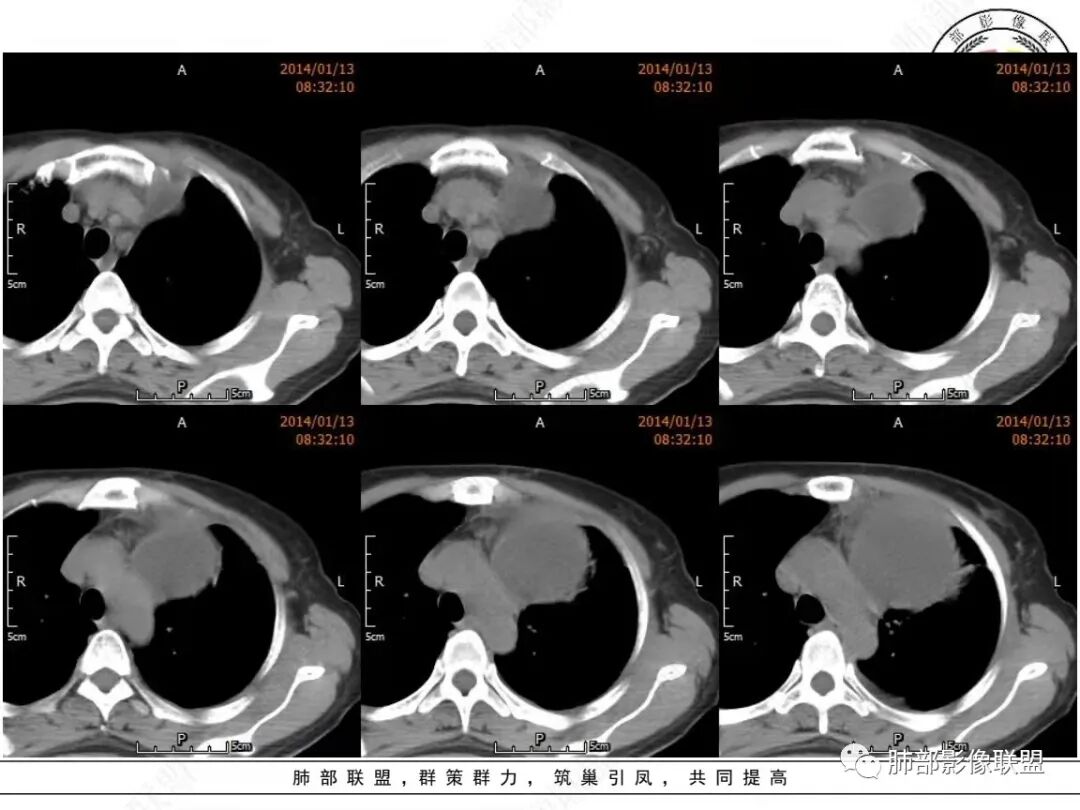

真人:中老年女性,左前纵隔囊实性占位,边界比较清晰,肺组织受压改变,考虑良性病变,囊性胸腺瘤?鉴别囊性畸胎瘤

宇宙:左前中纵隔囊性肿块伴壁结节,结节强化,边缘光整,邻近血管及左侧支气管受压,左侧胸水,考虑囊性胸腺瘤

空格:病灶的后内下增厚的包膜未见连续,纵隔脂肪浑浊密度增高、左侧胸腔积液,开始出现前胸后背的疼痛,完全可以用囊性灶破裂,引起化学刺激来解释。  不然看着软趴趴的病灶,既不可能是转移或侵犯胸膜引起的积液,也不像单纯纵隔或胸腺脓肿,因为白细胞不高。囊肿破裂是最好的解释。  这点就是手术指征。   定性  良性。    分析下来源:  1 这个部位常见的囊实性病灶有 囊性畸胎瘤、胸腺瘤出血囊变、支气管囊肿伴感染,淋巴管来源(前无神、后无皮,神经源性肿瘤不用考虑)。从发病年龄看,胸腺瘤>畸胎瘤,从壁结节强化后面丝丝拉拉的强化看,畸胎瘤可能大。两者都可以接受。综合囊性畸胎瘤破裂大于胸腺瘤出血囊变

衡妈:老年女性,定位是关键。左前中纵隔囊实性占位,囊性为主,囊壁厚薄不均,局部内壁可见壁结节,增强中等强化。考虑囊性畸胎瘤,鉴别胸腺瘤。

Dr. xiao:成熟囊性乏脂性畸胎瘤可能,增强只看到一期(动脉晚期),如果能有两期,能看到囊壁结节动态增强方式,确定囊变结节以发育成熟的畸形血管团为主,影像上出现静脉期强化程度的进一步加强,就更有把握

放射线:左侧纵隔囊性占位,可见壁结节,与纵膈结构分界不清,左肺组织受压,左侧内乳动脉增粗,壁结节明显强化,左侧胸腔积液,考虑囊性畸胎瘤,鉴别胸腺瘤?甲状腺来源肿瘤?